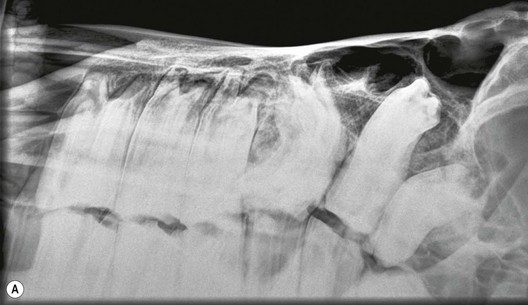

Vertical impaction of cheek teeth (‘eruption cysts’; ‘3 year-old and 4-year-old bumps’)

As noted in the previous section, many horses develop focal, bilateral swellings of their mandible and also less obviously (due to the presence of overlying muscles) of their maxillae beneath the developing apices of the 07 and 08 CT (Fig. 8.28). Certain breeds, especially lighter breeds and miniature breeds in particular, are more prone to develop these bony swellings. These eruption cysts may be due to vertical impaction of the CT that erupt last and a study showed increased angulation of the two adjacent CT onto mandibular CT with apical infection.36 With time, as the mandible and maxillae lengthen, the impacted CT have room to erupt normally and the overlying bones then remodel to a normal contour over the following year or so. Occasionally, the impacted tooth may become ankylosed to the ventral mandibular cortex and never erupt (Fig 8.29).

image

Fig. 8.28 This 4-year-old horse has bilateral eruption cysts beneath the lower 07s and 08s.

image image

Fig. 8.29 (A) Diagrammatic representation of overcrowding and vertical impaction of a mandibular 08. (B) Radiograph of a vertically impacted 307 that has become ankylosed to the ventral mandibular cortex. Additionally, marked drifting of the two adjacent teeth (306, 308) more occlusally now permanently prevents its eruption.